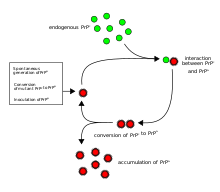

The first hypothesis that tried to explain how prions replicate in a protein-only manner was the heterodimer model.[50] This model assumed that a single PrPSc molecule binds to a single PrPC molecule and catalyzes its conversion into PrPSc. The two PrPSc molecules then come apart and can go on to convert more PrPC. However, a model of prion replication must explain both how prions propagate, and why their spontaneous appearance is so rare. Manfred Eigen showed that the heterodimer model requires PrPSc to be an extraordinarily effective catalyst, increasing the rate of the conversion reaction by a factor of around 1015.[51] This problem does not arise if PrPSc exists only in aggregated forms such as amyloid, where cooperativity may act as a barrier to spontaneous conversion. What is more, despite considerable effort, infectious monomeric PrPSc has never been isolated.[citation needed]

An alternative model assumes that PrPSc exists only as fibrils, and that fibril ends bind PrPC and convert it into PrPSc. If this were all, then the quantity of prions would increase linearly, forming ever longer fibrils. But exponential growth of both PrPSc and of the quantity of infectious particles is observed during prion disease.[52][53][54] This can be explained by taking into account fibril breakage.[55] A mathematical solution for the exponential growth rate resulting from the combination of fibril growth and fibril breakage has been found.[56] The exponential growth rate depends largely on the square root of the PrPC concentration.[56] The incubation period is determined by the exponential growth rate, and in vivo data on prion diseases in transgenic mice match this prediction.[56] The same square root dependence is also seen in vitro in experiments with a variety of different amyloid proteins.[57]

Until 2015 all known mammalian prion diseases were considered to be caused by the prion protein, PrP; in 2015 multiple system atrophy was found to be transmissible and was hypothesized to be caused by a new prion, the misfolded form of a protein called alpha-synuclein.[9] The endogenous, properly folded form of the prion protein is denoted PrPC (for Common or Cellular), whereas the disease-linked, misfolded form is denoted PrPSc (for Scrapie), after one of the diseases first linked to prions and neurodegeneration.[33][14] The precise structure of the prion is not known, though they can be formed spontaneously by combining PrPC, homopolymeric polyadenylic acid, and lipids in a protein misfolding cyclic amplification (PMCA) reaction even in the absence of pre-existing infectious prions.[59] This result is further evidence that prion replication does not require genetic information.[76]

It has been recognized that prion diseases can arise in three different ways: acquired, familial, or sporadic.[77] It is often assumed that the diseased form directly interacts with the normal form to make it rearrange its structure. One idea, the "Protein X" hypothesis, is that an as-yet unidentified cellular protein (Protein X) enables the conversion of PrPC to PrPSc by bringing a molecule of each of the two together into a complex.[78]